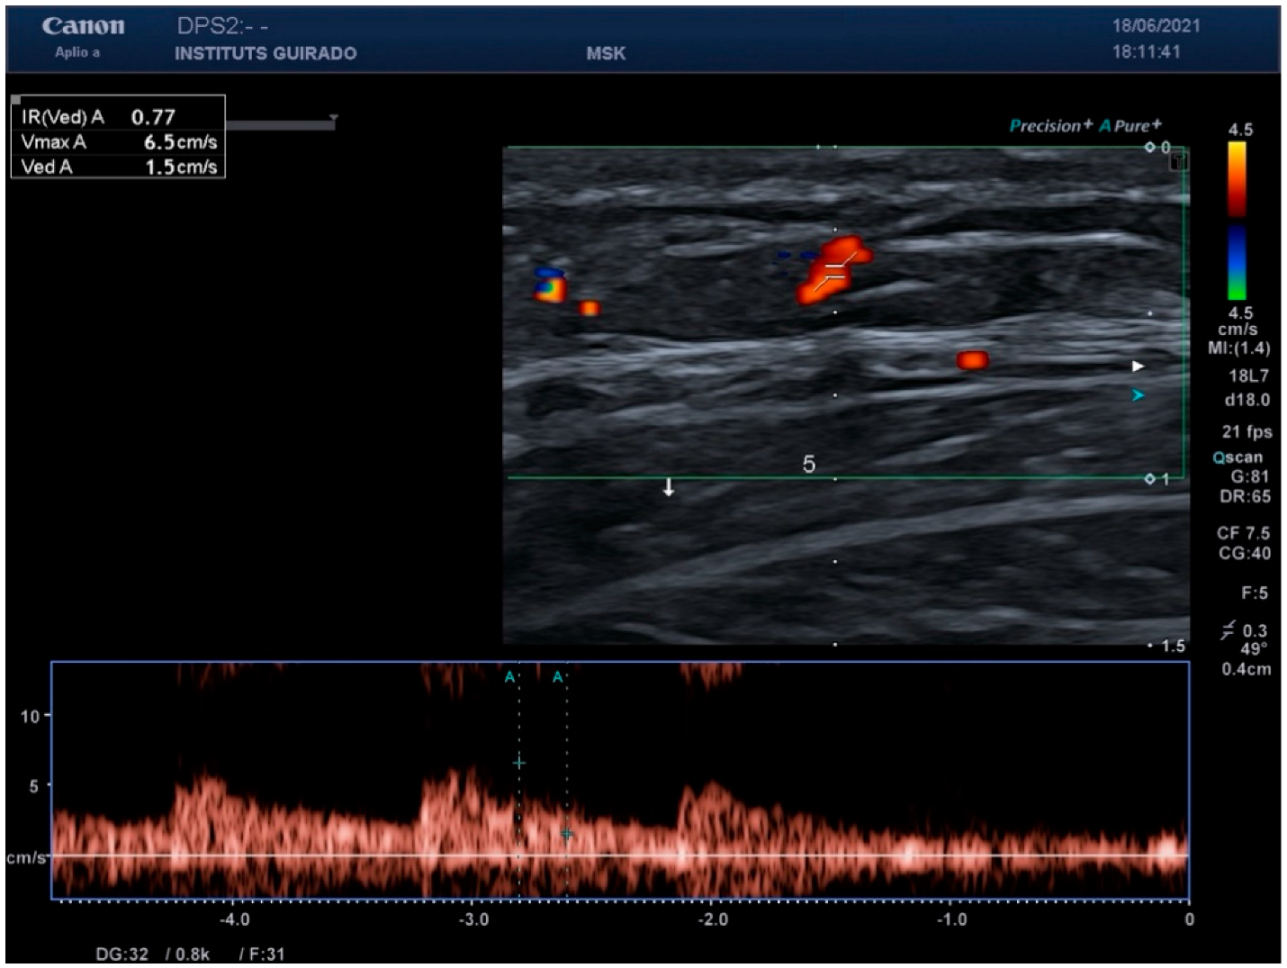

| Peak systolic (cm/s) | 6.5 (5.7–8.8) | 4.6 (3.5–6.8) |

| Resistance index | 0.71 (0.67–0.74) | 0.68 (0.59–0.75) |

| Vessel diameter (mm) | 0.78 (0.58–0.99) | 0.52 (0.37–0.78) |